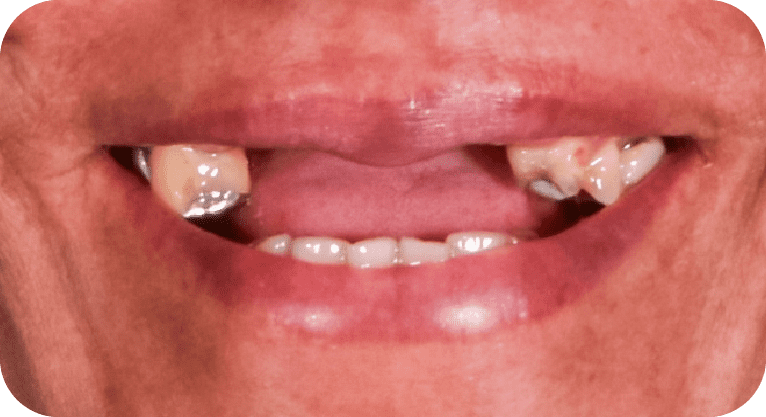

Paciente masculino, “33” años

Tratamiento: Diseño de sonrisa

El paciente presentó inconformidad con la estética de sus dientes anteriores. Tras un diagnóstico clínico y análisis digital, se realizó diseño de sonrisa con carillas de porcelana para corregir forma, posición y tamaño dental, logrando una apariencia armónica y natural que cumplió con sus expectativas estéticas.